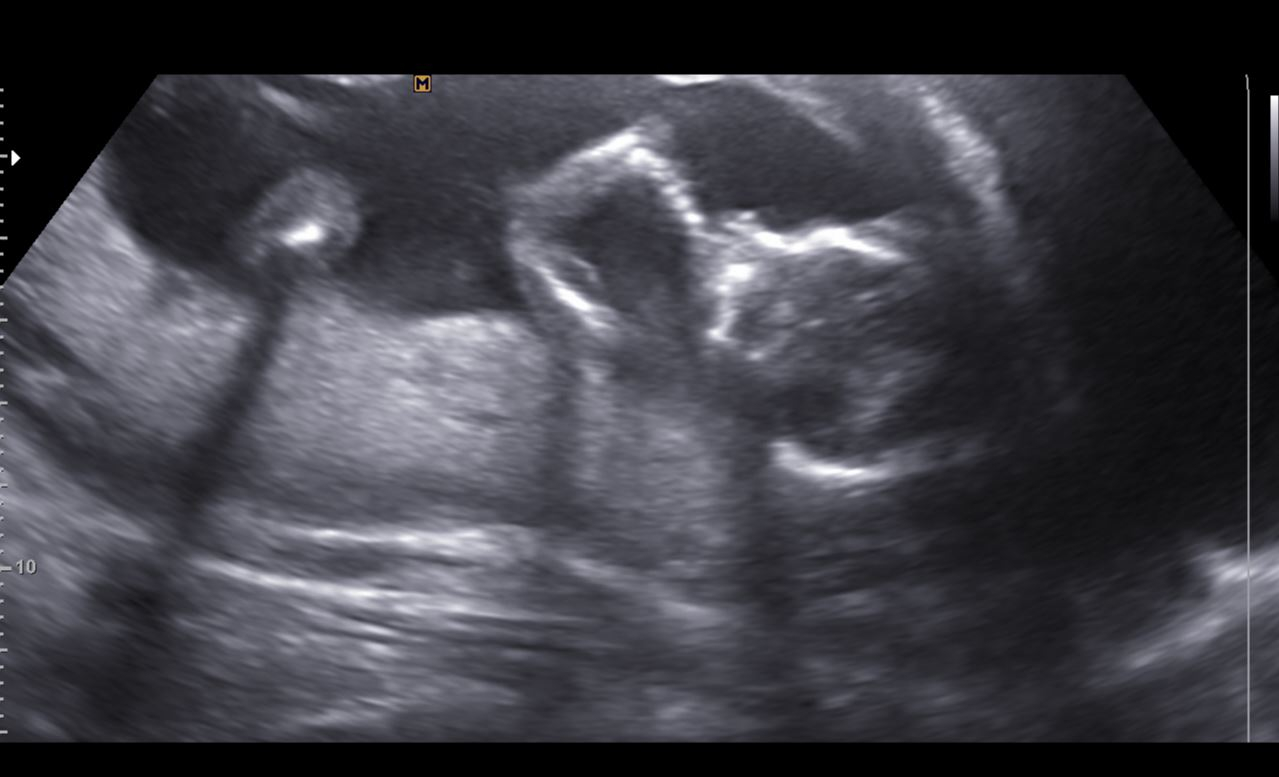

Healthy baby with the hematoma gone! Based on LMP would be 12w5d, based on previous ultrasounds they have me at 11w5d, baby measured 13w1d...we will see if EDD gets moved again. heart rate of 159.